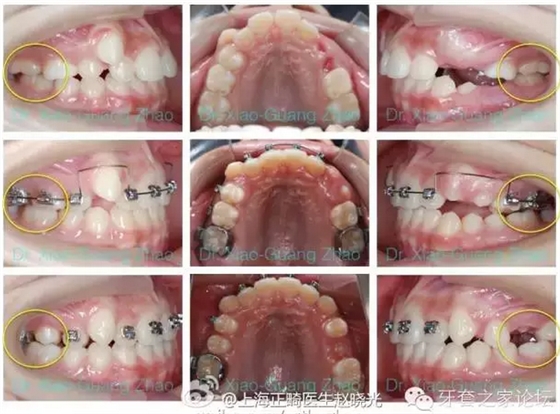

推磨牙向后一般是指推上頜磨牙向后,該技術(shù)在后牙咬合關(guān)系輕度錯(cuò)位,且上前牙存在輕度前突或輕中度擁擠的情況下使用。

如果能在上頜第二磨牙萌出之前開始治療,效果能夠更好。

(一)擺式矯治器結(jié)合固定矯治器,1992年有Hilgers發(fā)明。其特點(diǎn)是效果明顯,但推磨牙向后的作用多來源于磨牙的向后傾斜,因此比較容易在固定矯治階段復(fù)發(fā)。歡迎參見2005年4月我發(fā)表在“華西口腔醫(yī)學(xué)雜志”上的文章。